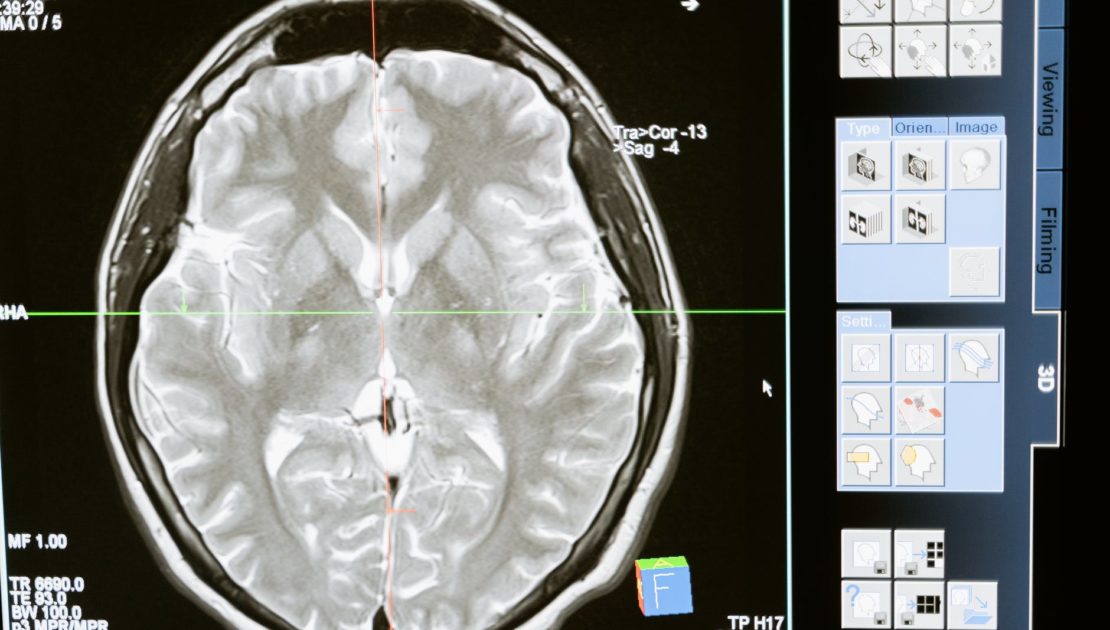

Do dzisiaj naukowcy nie wiedzą co wywołuje PTSD, ale większość hipotez mówi o udziale w nim, omawianej w artykule struktury. Związane to jest częściowo z wynikami neuroobrazowania mózgów pacjentów z zespołem stresu pourazowego, na którym widać hiperaktywność ciała migdałowatego podczas obserwacji bodźców skojarzonych z przeżyciem powodującym PTSD. Również często jest ono nadaktywne przy zetknięciu z różnymi innymi czynnikami wywołującymi strach. Zakłada się, że owa nadaktywność powoduje pobudzenie struktury i sprawia, że wspomnienia zdarzenia, wydają się mózgowi równie niebezpieczne jak w czasie gdy go doświadczał. U tych pacjentów kora przedczołowa nie jest w stanie wyciszyć reakcji emocjonalnej, jak to ma miejsce u zdrowej osoby.